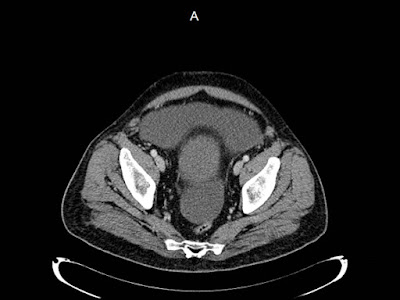

Mujer de 57 años.

Cuadro clínico de 1 mes de evolución caracterizado por distensión abdominal e hiporexia.